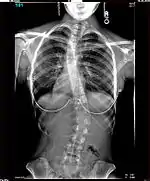

The Harrington Rod, or Harrington implant, is a device for the straightening of the spine inside the body, designed by Paul Harrington. The device consists of a stainless steel rod, attached to the spine at the top and bottom of the curve with hooks. Attached ratchets are then tightened to distract or straighten the spine. Following surgery to insert the rod, the patient wears a postoperative plaster cast or brace for a few months, until vertebral fusion has occurred, after which the cast or brace is removed.[5]

The major drawback of the Harrington Rod is that it straightens out the normal front to back curvature of the segment of the spine that is fused, which in many patients results in a flat back deformity, also known as "flatback syndrome". Advances in surgical techniques and technology in the late 1990s were eventually able, in most cases, to correct scoliosis without causing flatback syndrome, leading to the gradual phasing out of the Harrington Rod.[6]